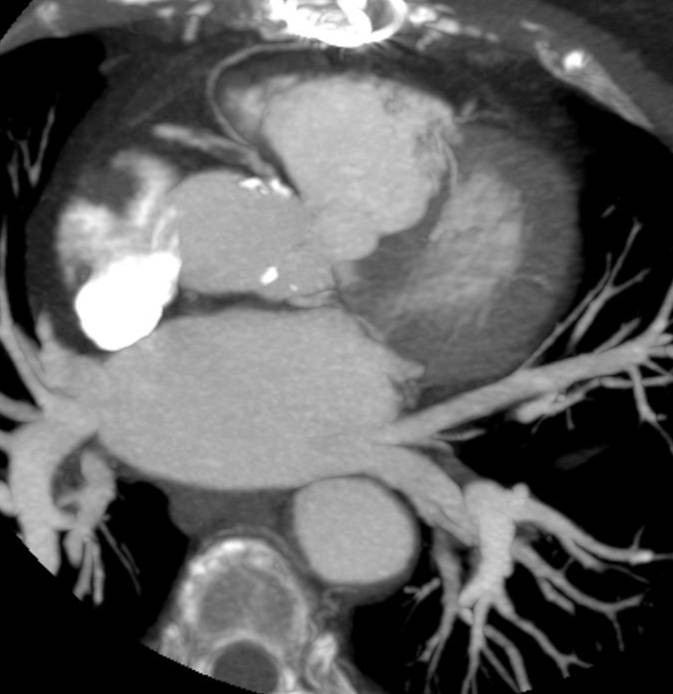

The non-invasive imaging modality of multi-detector computed tomography has dramatically evolved the last ten years and that is due to hardware and software developments. The newer generation of scanners allows increased spatial and temporal resolution that improves the clinical reliability giving further insights into the evaluation of coronary artery disease. Heart morphology imaging followed by studies of myocardial function and assessment of cardiac valves can be performed from the information derived from the data of the coronary artery examination. Also, the venous anatomy of the heart, coronary artery bypass grafts, stents, and cardiac tumors can be imaged and evaluated when necessary. For the beneficial use of this method, entrance criteria for different patient groups need to be set in order to allow improved outcome of multi-detector CT.